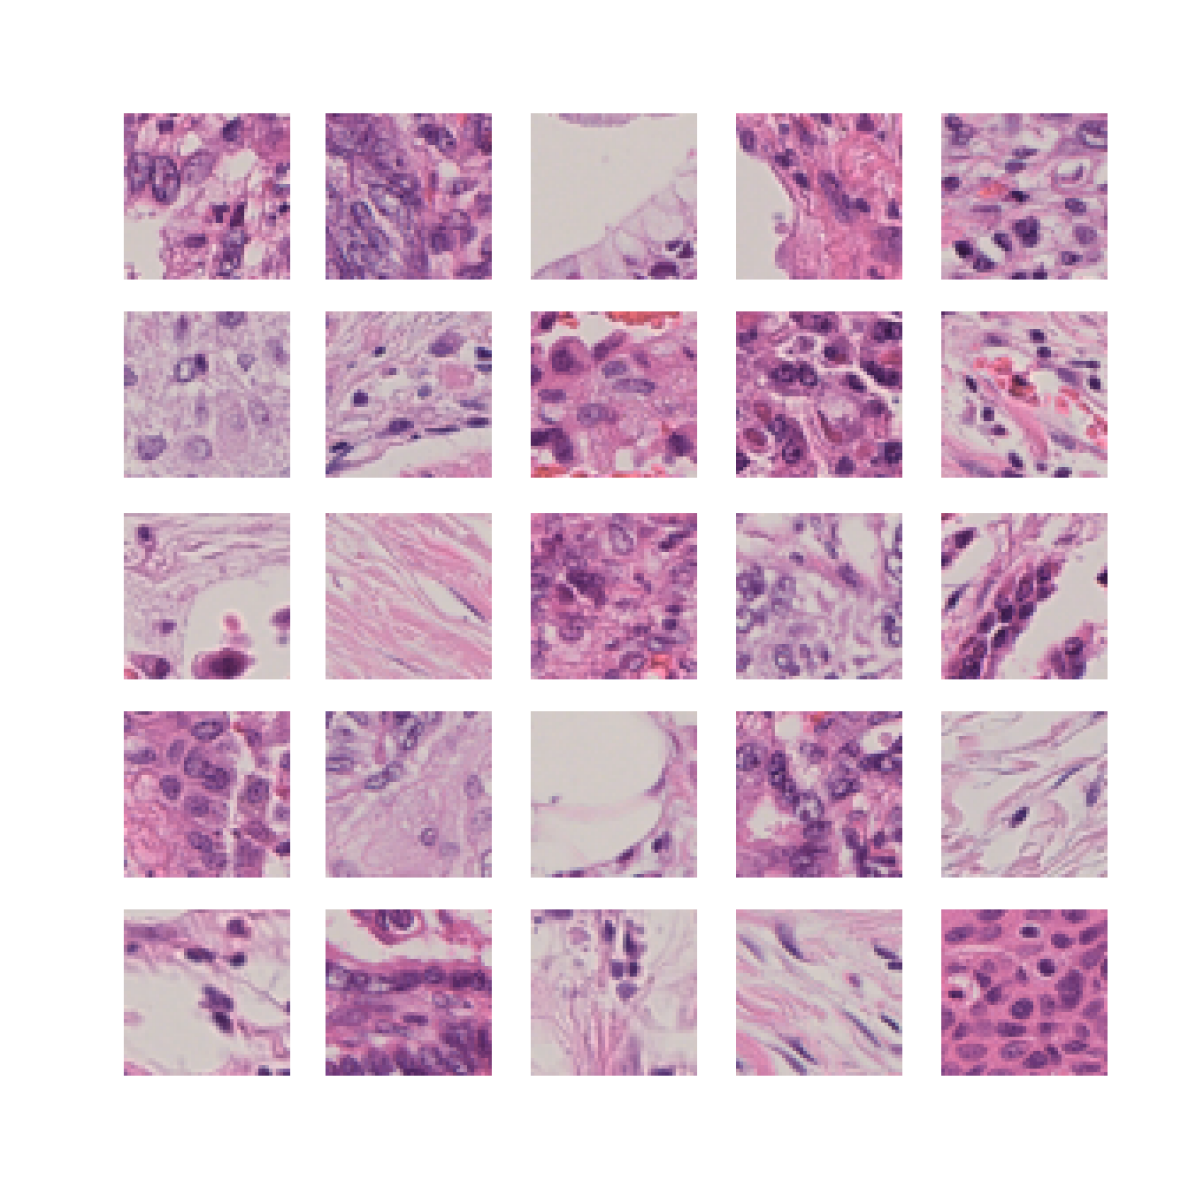

S1.1 Histology

To analyse tissue samples, pathologists take slices of tissue around 5m thick to be analysed under a microscope. To make it easier to identify different structures, the slide is typically stained with chemicals that bind tightly to different components of the sample, dying them different colours. By far the most common staining method used in histopathology is haematoxylin and eosin (H&E) staining. Haematoxylin stains components that are rich in nucleic acids, such as nuclei and ribosomes, while Eosin stains common protein structures pink, such as connective tissue, collagen, and the cytoplasm [54].

Immunohistochemistry is an ancilliary staining technique often used in medical diagnosis, which works by using an antibody to target specific proteins in tissue. Secondary chemical processes are coupled to the antibody to produce a colour, making it much easier to identify their presence and location within tissue. There are many different antibodies used which each target a specific protein or protein type. Common examples of antibody targets include cytokeratins, which are found in epithelial cells, CD3, CD4, and CD20, which are found in various types of immune cells, and smooth muscle actin (SMA), which is found in myofibroblasts [55].

Typically these stains are highly informative about one particular protein of instance, but lack the generality of H&E staining. Consequently, they are primarily used as secondary sources of information to assist with research or diagnosis.

While H&E staining is the routine protocol for tissue analysis, pathologists usually rely on IHC or IF staining to obtain information about the locations of individual proteins, which may aid further investigation or confirm their diagnoses. IHC and IF stains therefore contain highly specific information about a particular protein, so add useful information beyond that which can be readily identified with H&E staining. While this is necessary for human pathologists to identify features which cannot be easily identified by eye in the generic H&E stains, for example separating the identities of individual epithelial, endothelial, myeloid cells and lymphocytes, it has been shown that neural networks can accurately reproduce many of these stains from only H&E [39]. It would be tempting to conclude, then, that this is a solved problem, and researchers should simply use these models to produce representations of H&E patches which contain features relevant to IHC or IF stains. Unfortunately, this has been shown to perform poorly [19], as image to image translation models are restricted to learning very fine grained information, such as the exact locations of nuclei, at the expense of the types of low-redundancy coarse grained features which are learned by self-supervised Siamese networks.

Nevertheless, the results of these works imply that much or all of the useful information in IHC and IF stains can be predicted from H&Es. We investigate how representation are affected by distilling information from IHC and IF stains into models of H&E stains, evaluating both brightfield IHC images and thresholded IF images.

S2.1 SegPath

SegPath [22] is a large pan-cancer dataset containing 8 subsets corresponding to 8 different IF stains with paired H&E stains, which are detailed in Table S1. Stains were performed individually on each slide, not multiplexed, and H&Es were obtained from the same section as the IF by initially staining with H&E, then washing the slides and restaining with the IF stain. Different slides were used for each stain, so there is inter-subset variability between the image features present in the subsets. Slides were tissue microarrays featuring samples from cancer types including glioma, meningioma, ependymoma, kidney renal clear cell carcinoma, lung adenocarcinoma, lung squamous cell carcinoma, breast adenocarcinoma, gastric adenocarcinoma, colon adenocarcinoma, pancreatic adenocarcinoma, cholangiocarcinoma, hepatocellular carcinoma, esophageal squamous cell carcinoma, head and neck squamous cell carcinoma, urothelial tumors, bladder cancer, prostate adenocarcinoma, sarcoma, melanoma, uterine cancer, ovarian tumors, and testicular germ cell tumors.

We paired H&E images with corresponding thresholded IF images of the same (restained) patch from the SegPath dataset [22]. IF images were obtained by thresholding IF intensity, such that pixels with lower intensity than the cutoff were labelled 0 and those higher than the cutoff were labelled 1. For ease of computing and consistency of size with evaluation datasets, we resized each px image to px with linear interpolation, and split these into 16 px patches, and did the same for each corresponding mask. Each input was a tuple , with both and being px (pixel) patches from the same location on both the H&E and restained slides. Given that no evaluation was to be performed directly on the SegPath dataset, the train, validation and test sets were combined to increase the dataset size, with the number of patches for each stain after preprocessing detailed in Table S1.